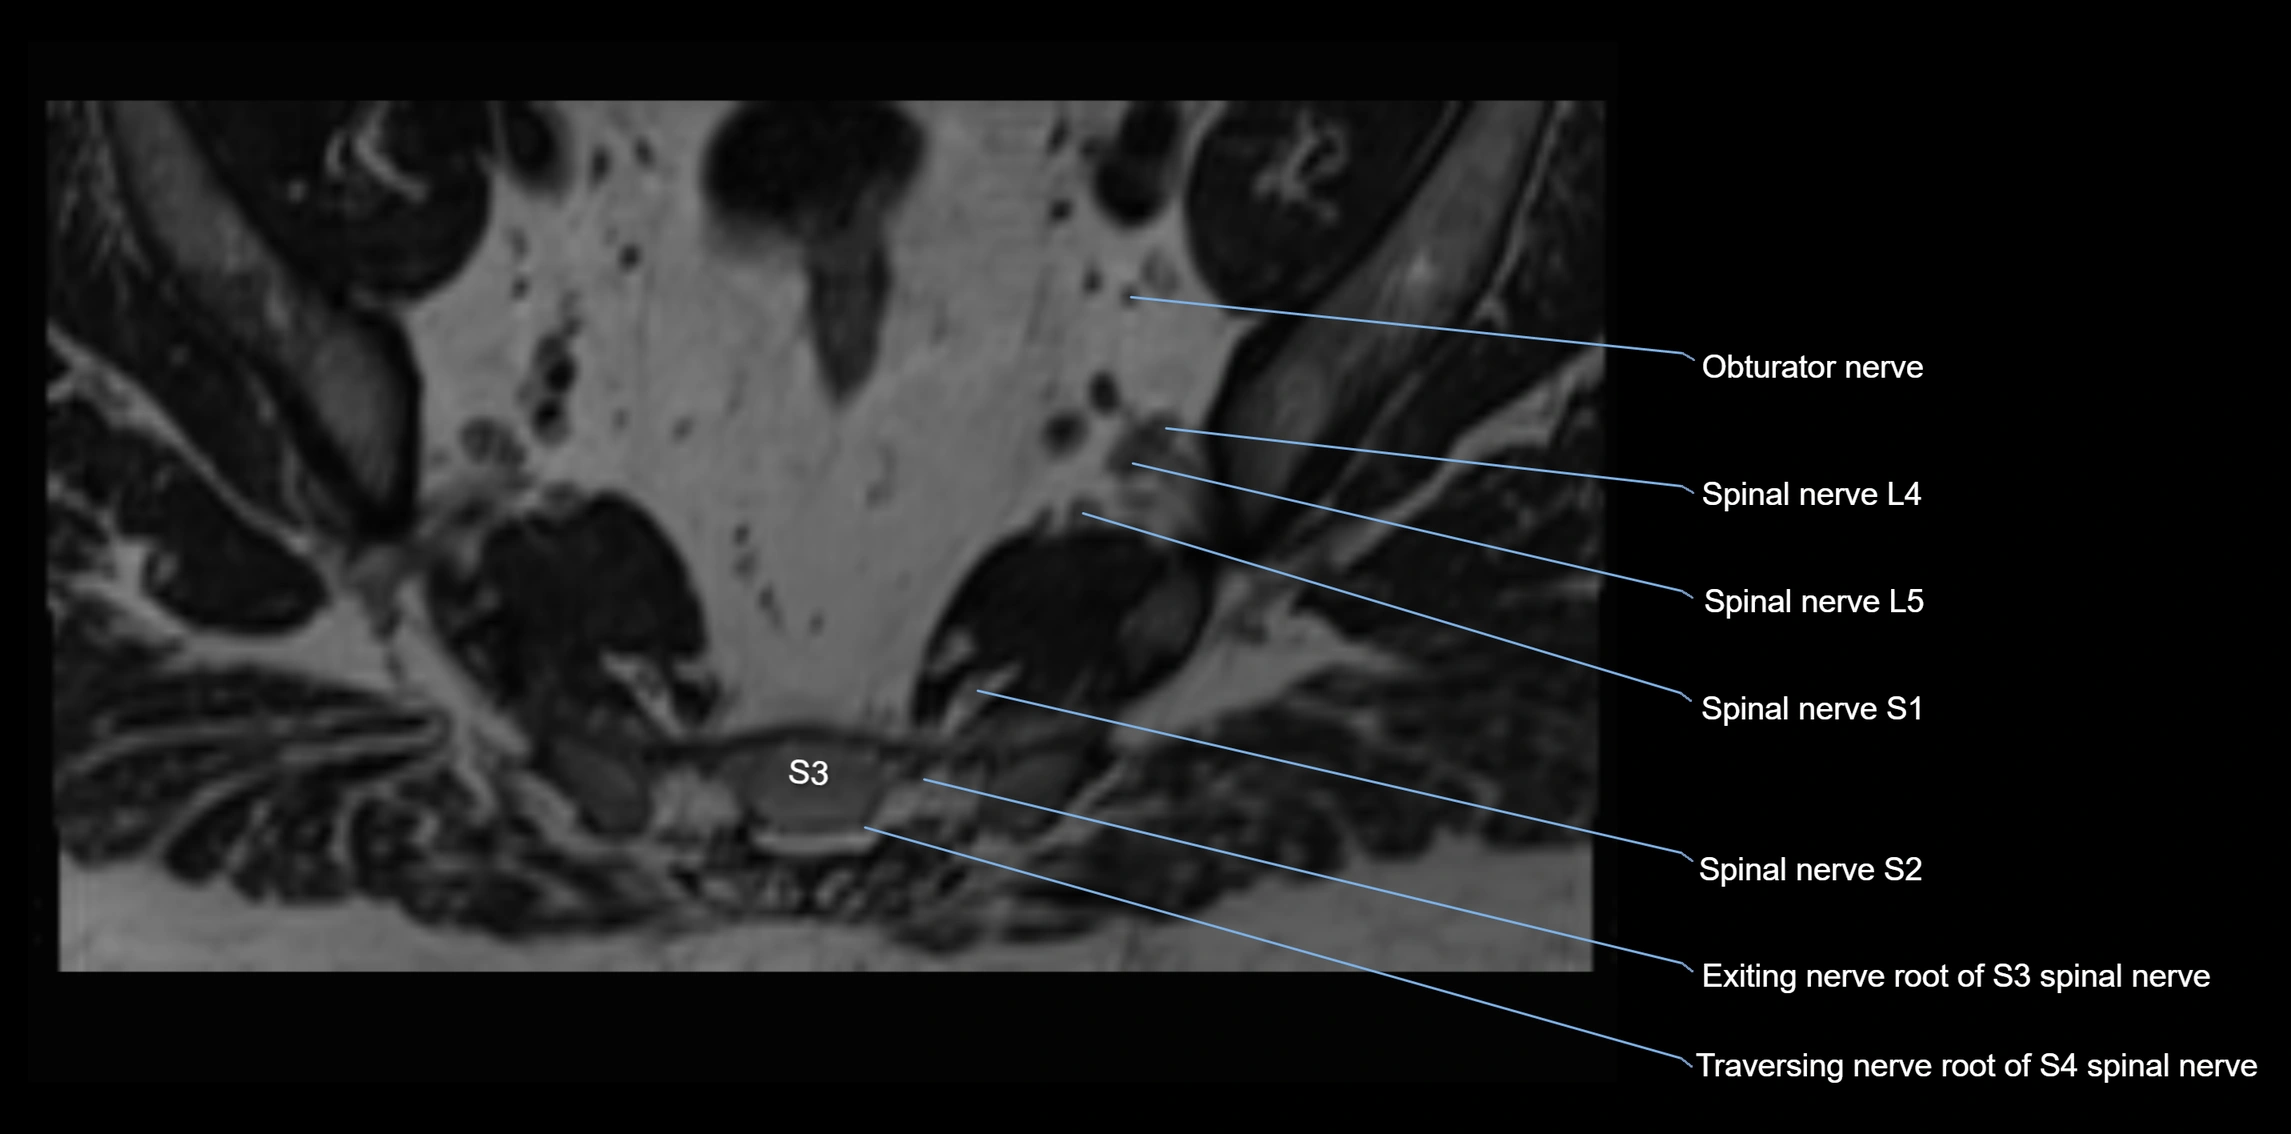

MRI image

image